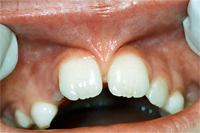

Ein seitlicher Oberkieferschneidezahn ist als sogenannter Zapfenzahn (angeboren) in die Mundhöhle durchgebrochen (Abb. 1). Nach orthodontischer Zahnbehandlung haben wir dem 16 Jahre alten Mädchen den Vorschlag gemacht, mittels zwei adhäsiv gelegten Kompositfüllungen und ohne Beschleifen den Zapfenzahn in einen natürlichen Schneidezahn umzuformen (Abb. 2).